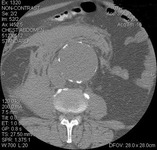

Type II endoleak (encircled) discovered on follow-up CT

University of Michigan, specifically the cases of Dr Upchurch reflecting the Departments of Vascular Surgery and Radiology